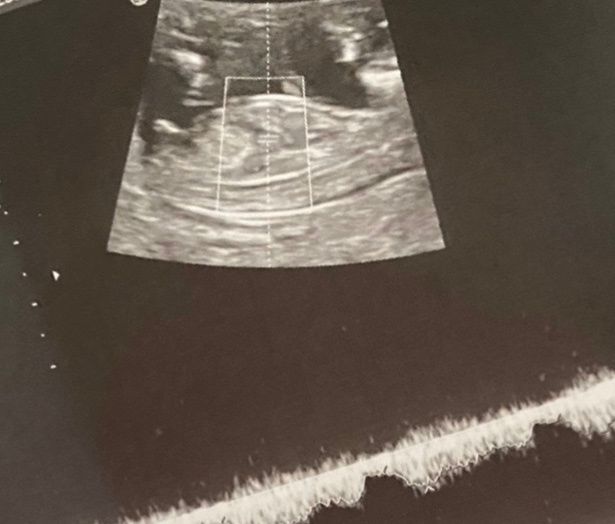

Ciao ragazze qualche gg fa ho scoperto di aspettare un maschietto anche se mi avevano detto prima che era femminuccia infatti sono rimasta abbastanza scioccata mente mi faceva l'ecografia.. mi ero fissata troppo mi sa! Vi allego le mie eco.. è sicuro...